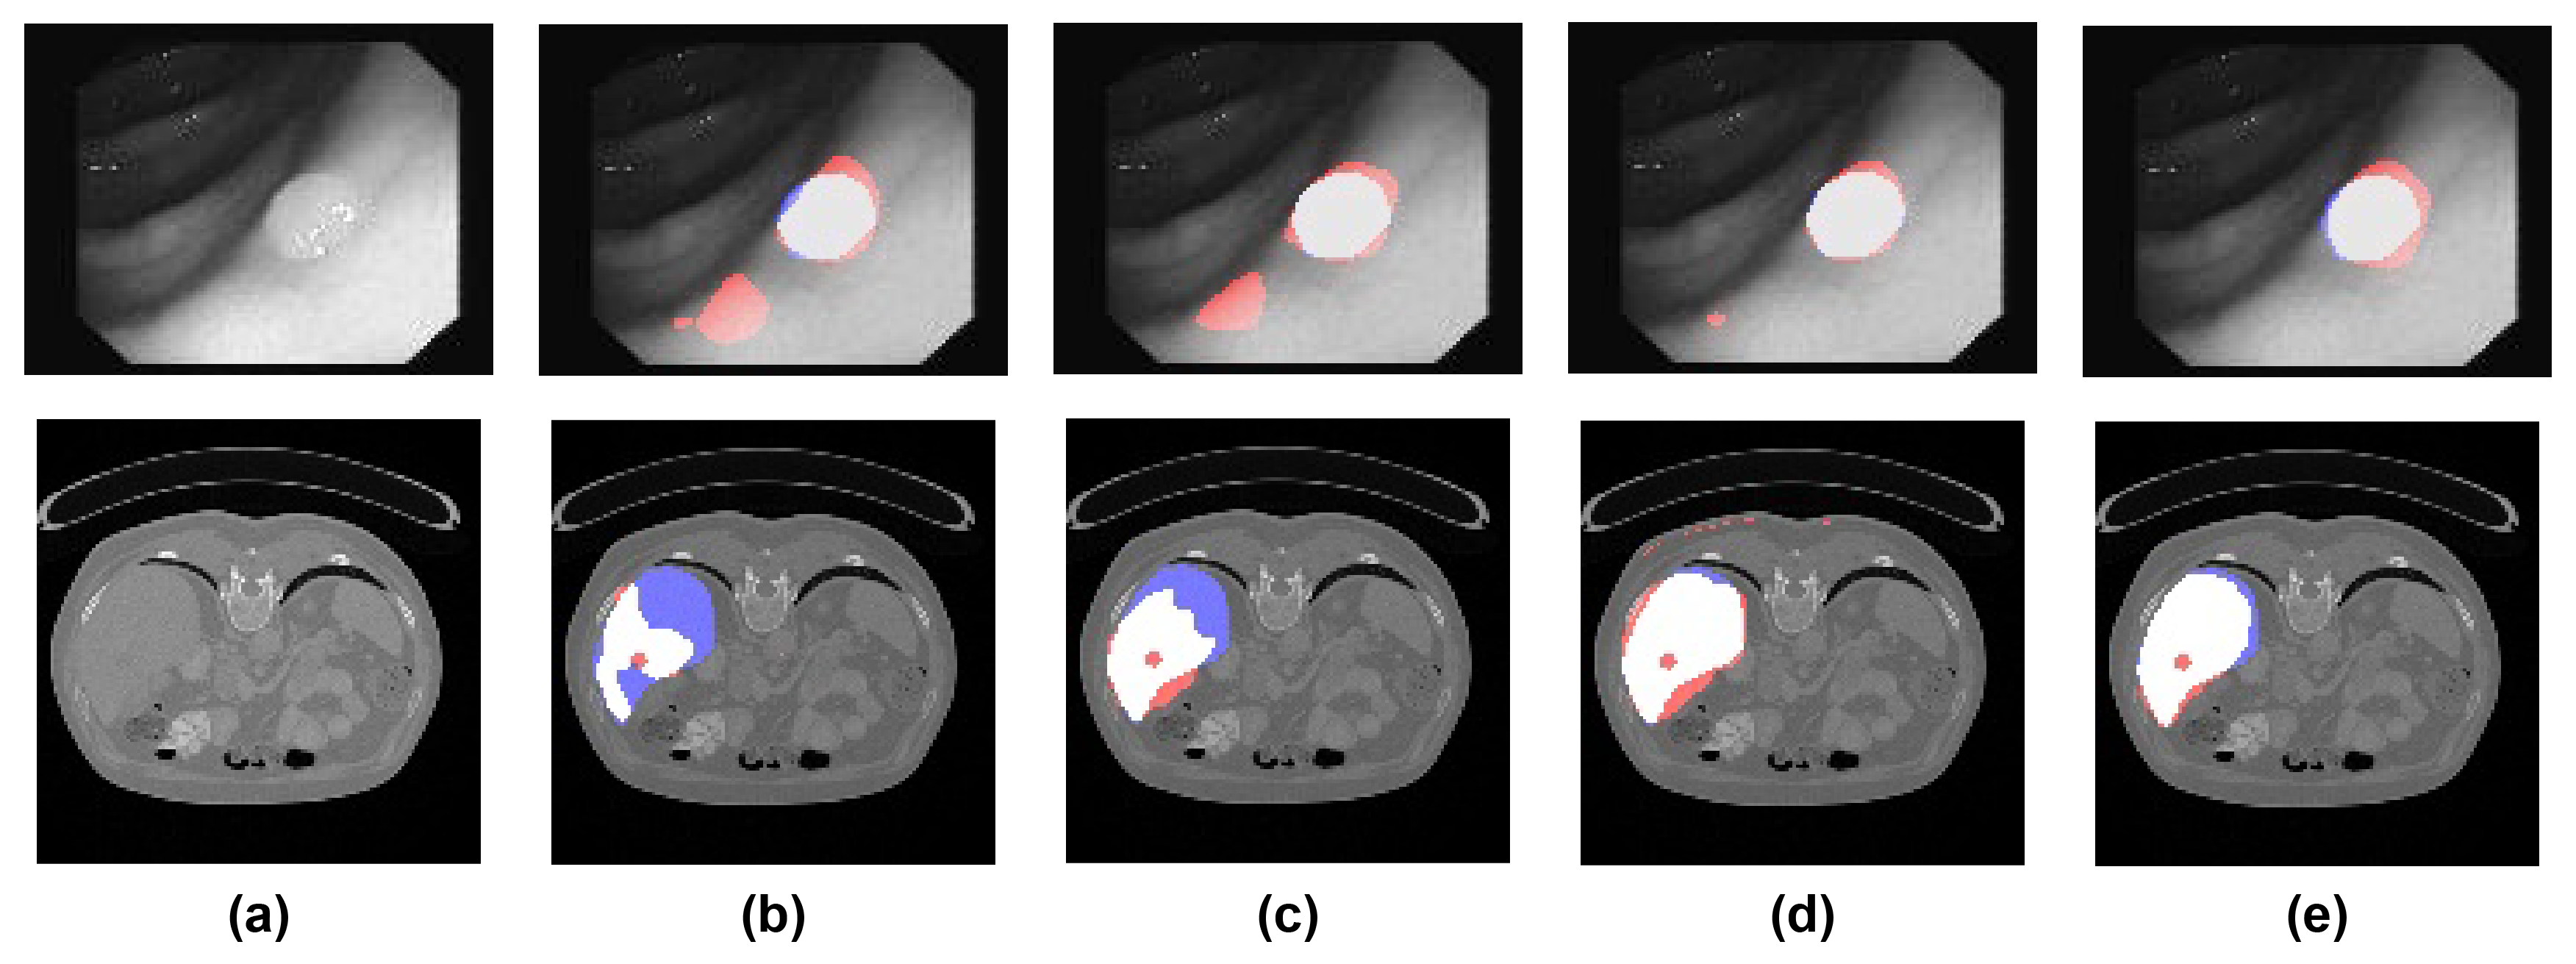

Figure 1: Qualitative analysis of image segmentation for different competing methods (best viewed in color). (a) original image; (b) U-Net [13]; (c) U-Net++ [17]; (d) SDU-Net (ours); (e) SDNU-Net (ours); (top row) polyp segmentation. The baseline U-Net architectures mistakenly identify a region in the bottom left corner as relevant due to the local features. However, when observing the image as a whole, it is clear that there is a single region of interest, as marked successfully by our networks. (bottom row) liver segmentation. In contrast to SDN-based networks, the baseline U-Net architectures are unable to coherently identify the well-shaped region of interest. (red color) false positives; (blue color) false negatives; (white color) correctly predicted pixels.

The performance of automatic medical image segmentation critically depends on the capability of machine learning algorithms to: (i) accurately identify intensity discontinuities or edges as object boundaries that characterize local textures; and (ii) account for global, contextual information when assessing the relevance of different image regions e.g. understanding image-specific semantics and texture. Convolutional neural networks excel at (i) but often fail at (ii) as examplified in Figure 1. We argue that the main reason is the intrinsically limited receptive field of convolutions coupled with the ’shallow’ architecture design typical in medical domain. This issue is common to practically all state-of-the-art architectures that are based on the U-Net-like design [13]. U-Net improves upon the vanilla encoder-decoder design by enabling fusion of textural features across distinct semantic levels; done by introducing skip connections between encoding and decoding paths at different levels and increasing the number of feature channels in the expansive path. However, none of the existing networks in the family of U-Nets is well-equipped to perform non-local similarity comparisons and provide spatially coherent, holistic image segmentation – one of the key characteristics of human-based medical image segmentation.

Globally, the inclusion of spatial dependency layers improves model performance in all evaluated segmentation tasks, with both SDU-Net and SDNU-Net obtaining enhanced performance comparatively to its baselines (average improvement of 4.29 Dice points and 4.47 Jaccard points). The vanilla U-Net is also outperformed in most metrics by our U-Net equipped with spatial dependency layers (SDU-Net). In both the colon polyp segmentation and the liver segmentation setting large improvements were shown between SDNU-Net and U-Net++, with a 6.98 Dice and 6.74 Jaccard gain for the polyp segmentation, and 5.48 Dice and 5.64 Jaccard increase for the liver segmentation. Arguably this may be due to the variable scales at which polyps and liver cross-sections appear, with large texture changes between both polyps and ’normal tissue’, i.e. non-tumoral, and liver and non-liver tissue. Qualitative comparison in Fig. 1 also corroborates this assertion.